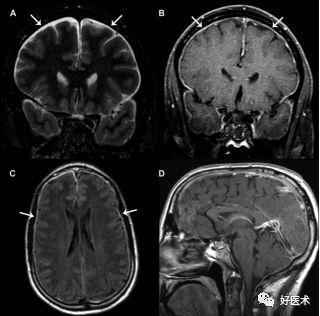

诊断